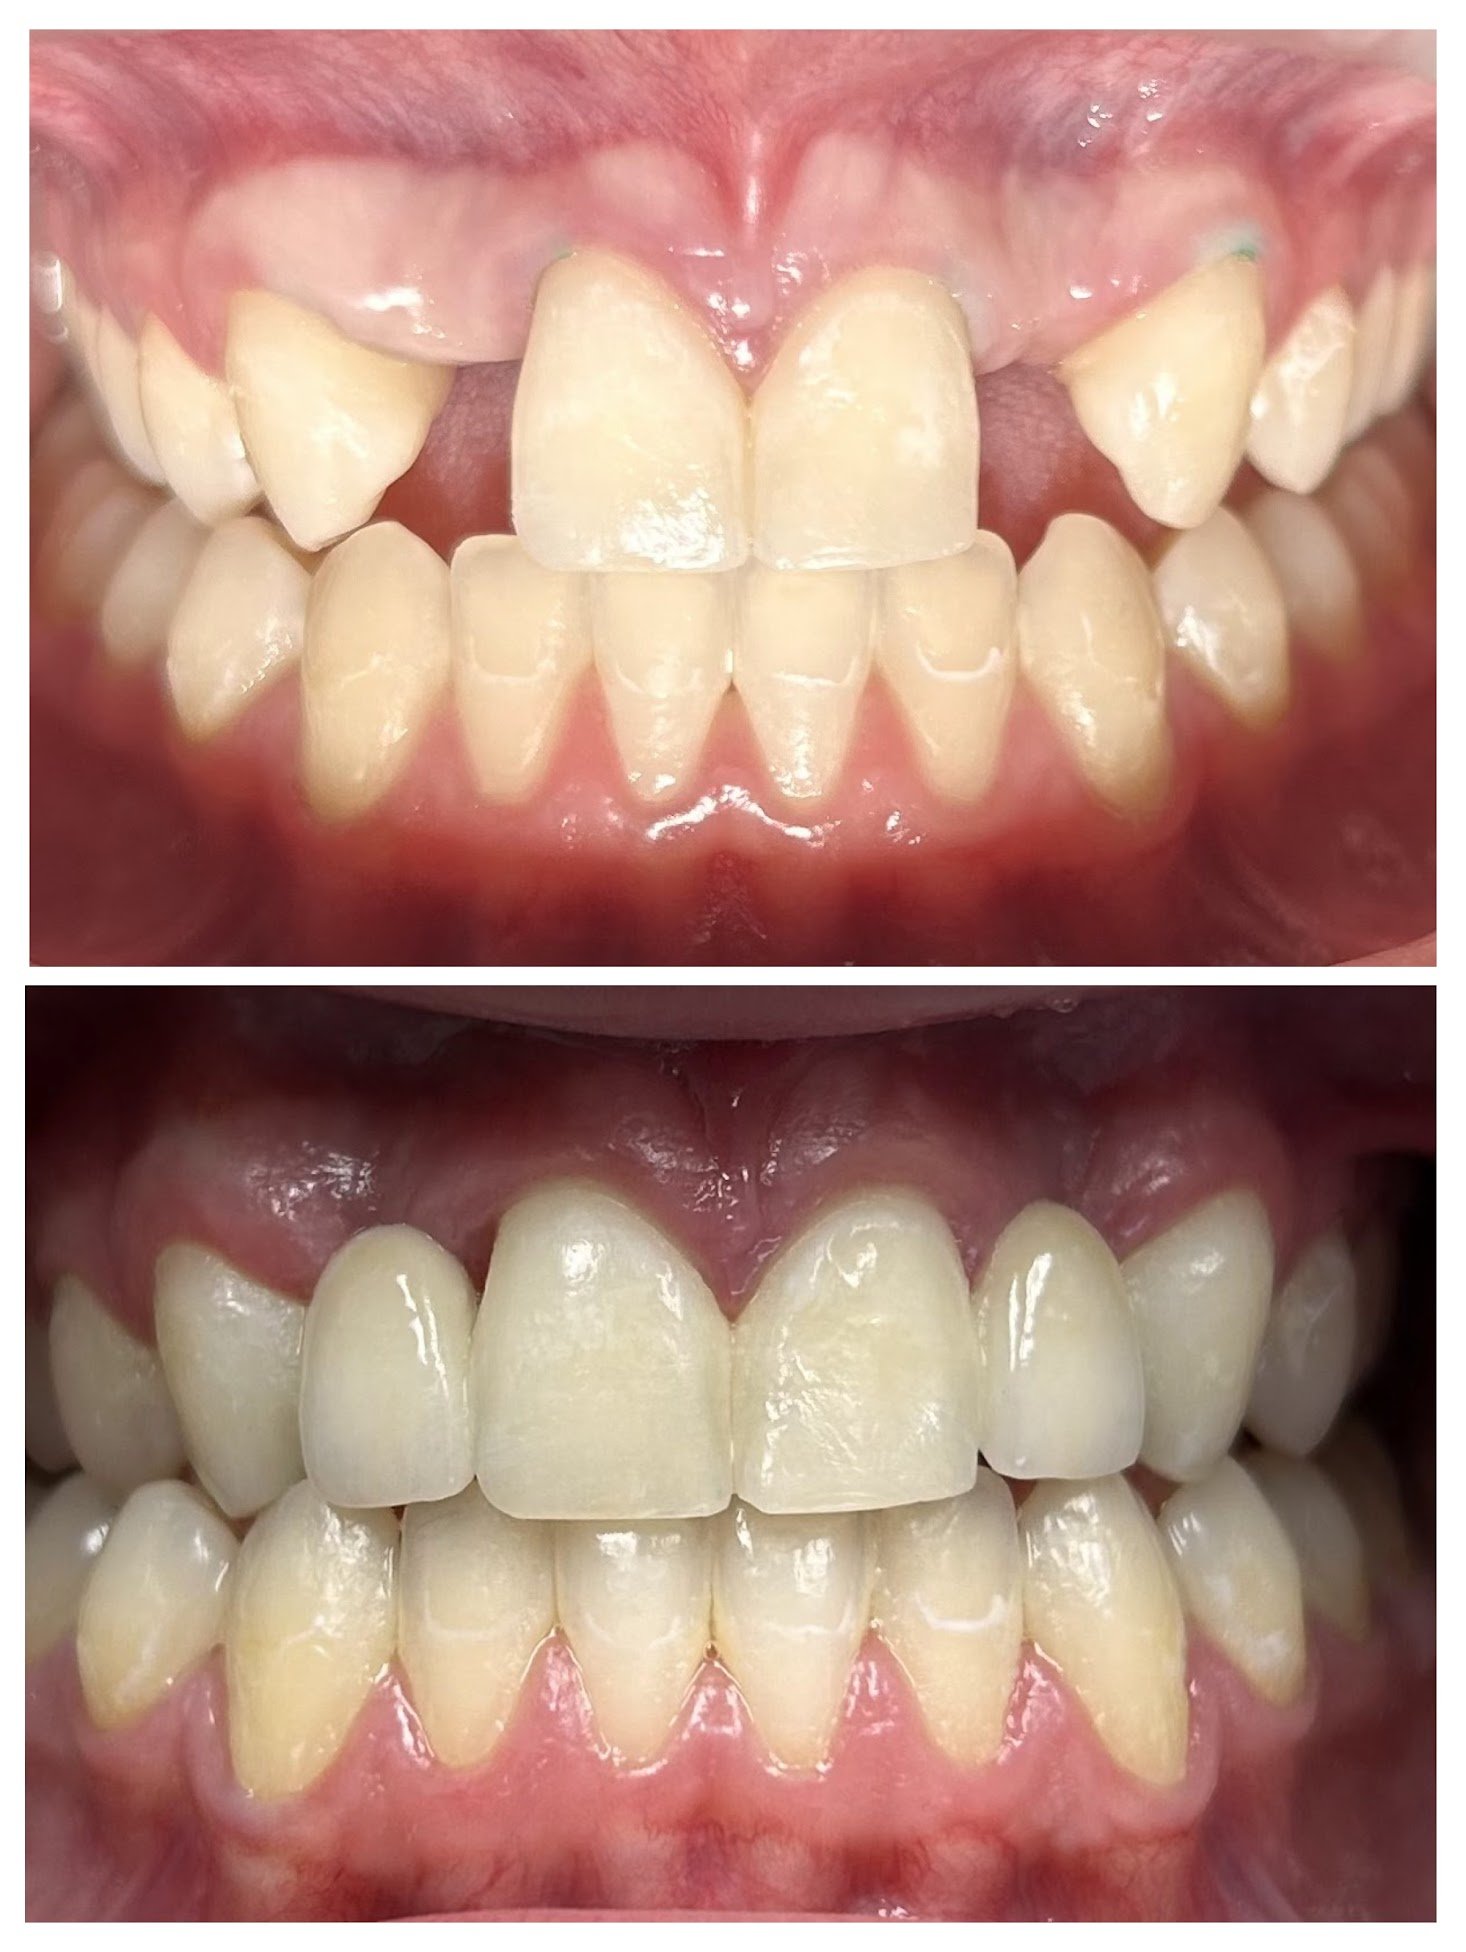

Orthodontics

Movement of teeth to improve function and appearance with Invisalign

Invisalign

Before and after appliance

Orthodontic Appliance